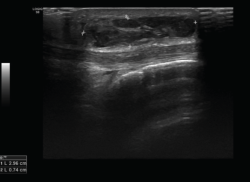

Tanto el ligamento lateral interno (LLI) como el ligamento lateral externo (LLE) pueden ser valorados por ecografía (Figura 7).

Figura 7. Corte coronal de una ecografía de rodilla. A: engrosamiento del ligamento lateral externo en la inserción proximal por un esguince de grado I; B: engrosamiento del ligamento lateral interno.